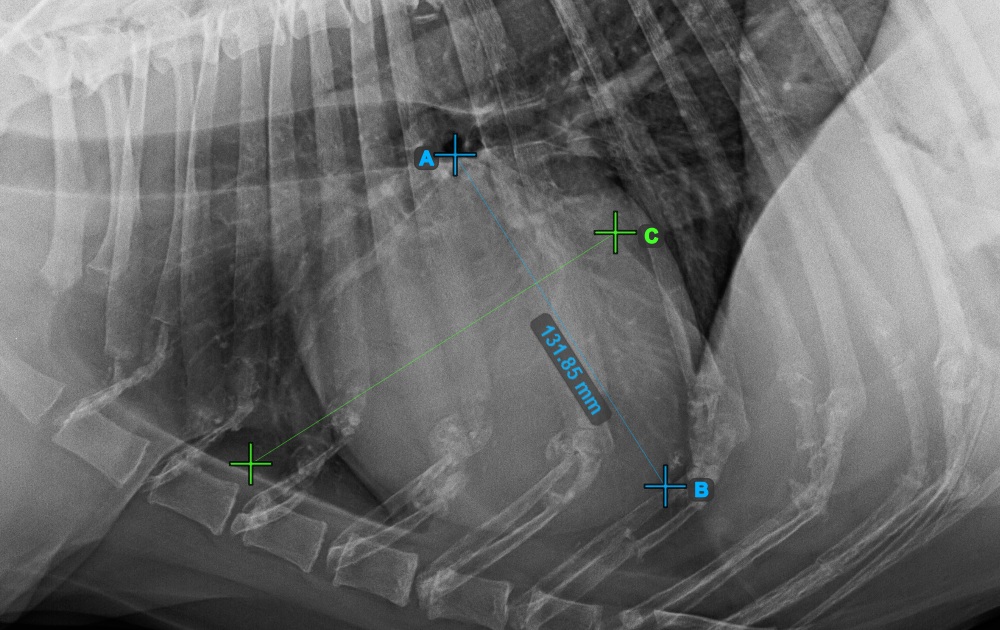

Complete the long axis of the heart by marking the Apex point, near the bottom of the heart.

The image below represents a typical placement of the Apex point.

../../_images/image394.jpg